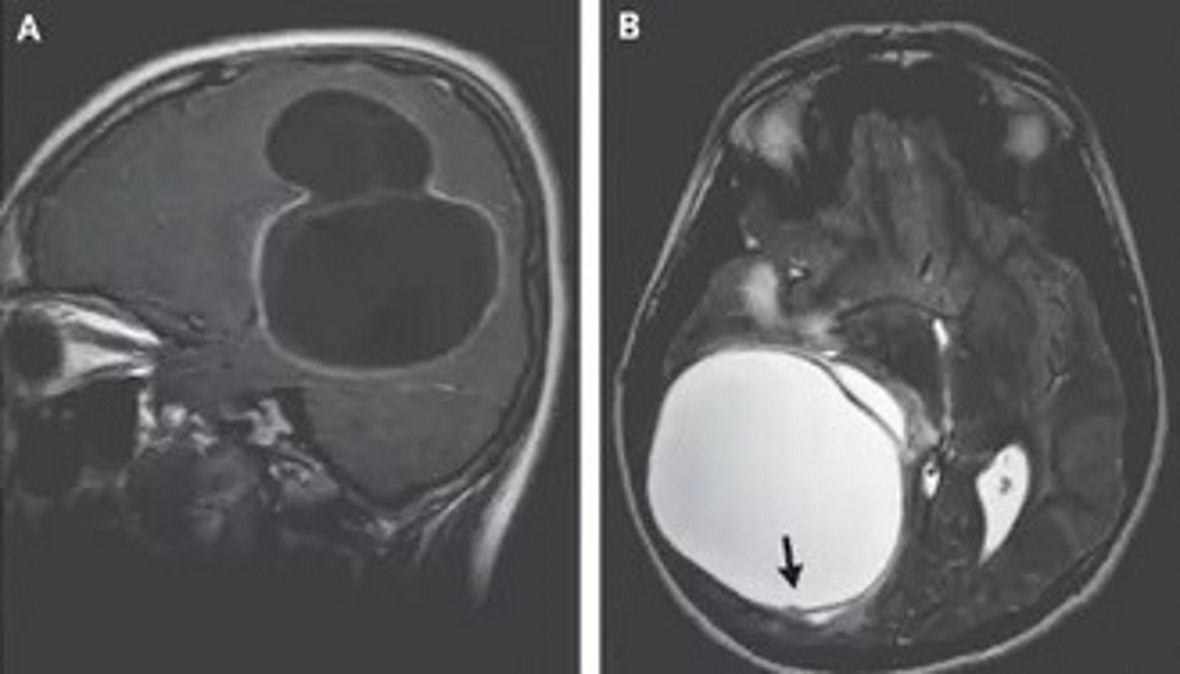

14-latek z Indii cierpiał na silne bóle głowy i nudności. Postanowił skonsultować swoje objawy z lekarzem. Po przeprowadzeniu badań okazało się, że nastolatek zaraził się tasiemcem bąblowcowym, na skutek czego w jego mózgu utworzyła się groźna torbiel.

Jak do tego doszło? Bąblowica to infekcja pojawiająca się po zjedzeniu pokarmu lub wypiciu wody, które zawierają jaja pasożyta z grupy Echinococcus. Nastolatek zaraził się tasiemcem najprawdopodobniej poprzez kontakt z zakażonym bydłem lub odchodami. Infekcja doprowadziła do powstania u niego dużej torbieli w mózgu. Tasiemce bąblowcowe występują na wszystkich kontynentach z wyjątkiem Antarktydy.

- Ludzie zarażają się poprzez przypadkowe połknięcie jaj tasiemca lub bliski kontakt z zarażonymi psami, żywym inwentarzem, lub poprzez spożycie wody bądź warzyw zanieczyszczonych odchodami zarażonych zwierząt. Po spożyciu larw tasiemca trafiają one zazwyczaj do wątroby lub płuc. Bardzo rzadko przedostają się do krwiobiegu. Torbiel tworzy się w mózgu pacjenta zaledwie w ok. 2 proc. przypadków - dodaje lekarz.

Wycięcie tak dużej torbielii nie było proste. Chirurdzy musieli wykonać zabieg kraniotomii, czyli usunięcia fragmentu kości czaszki. Lekarzom udało się usunąć zmianę w całości.

- W takim przypadku ważne jest, aby ostrożnie oderwać torbiel od tkanki mózgowej, nie rozrywając jej. Wyciek płynu z torbieli może spowodować rozprzestrzenianie się lub nawrót choroby, a czasem reakcję alergiczną zagrażającą życiu - podkreśla dr Thakar.

Na szczęście choroba nie spowodowała trwałych uszkodzeń w mózgu chłopca. Objawy, na które skarżył się nastolatek, całkowicie ustąpiły wkrótce po operacji. Po dwóch tygodniach od wypisania ze szpitala 14-latek wrócił do szkoły.